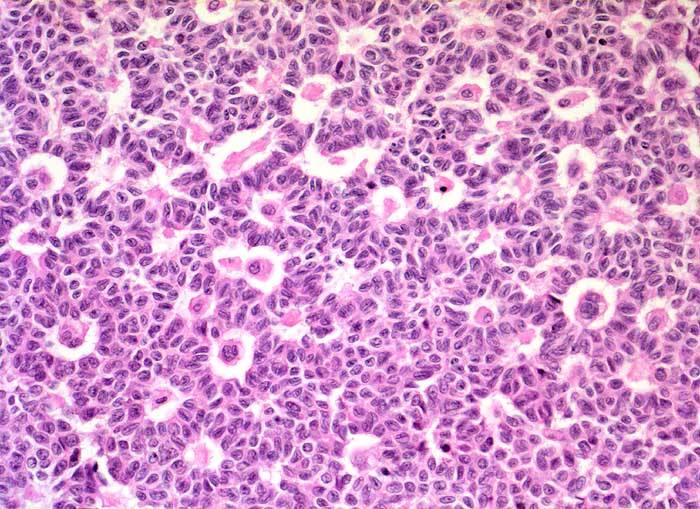

PathoPic ID 5331 - Granulosazelltumor vom adulten Typ des Ovars

Granulosazelltumor vom adulten Typ des Ovars

maligner Tumor

Ovar

Solides Tumorareal mit zahlreichen

Call Exner Körperchen. Die Tumorzellen zeigen längliche Kerne mit Kernkerben.

Die Tumorzellen zeigen eine Positivität für Inhibin und CD99, sind jedoch negativ für EMA.

Ovarial-Tumor links -> Adnexektomie links. Frage: Dignität? CA-125 im Normbereich.

Histologie

200